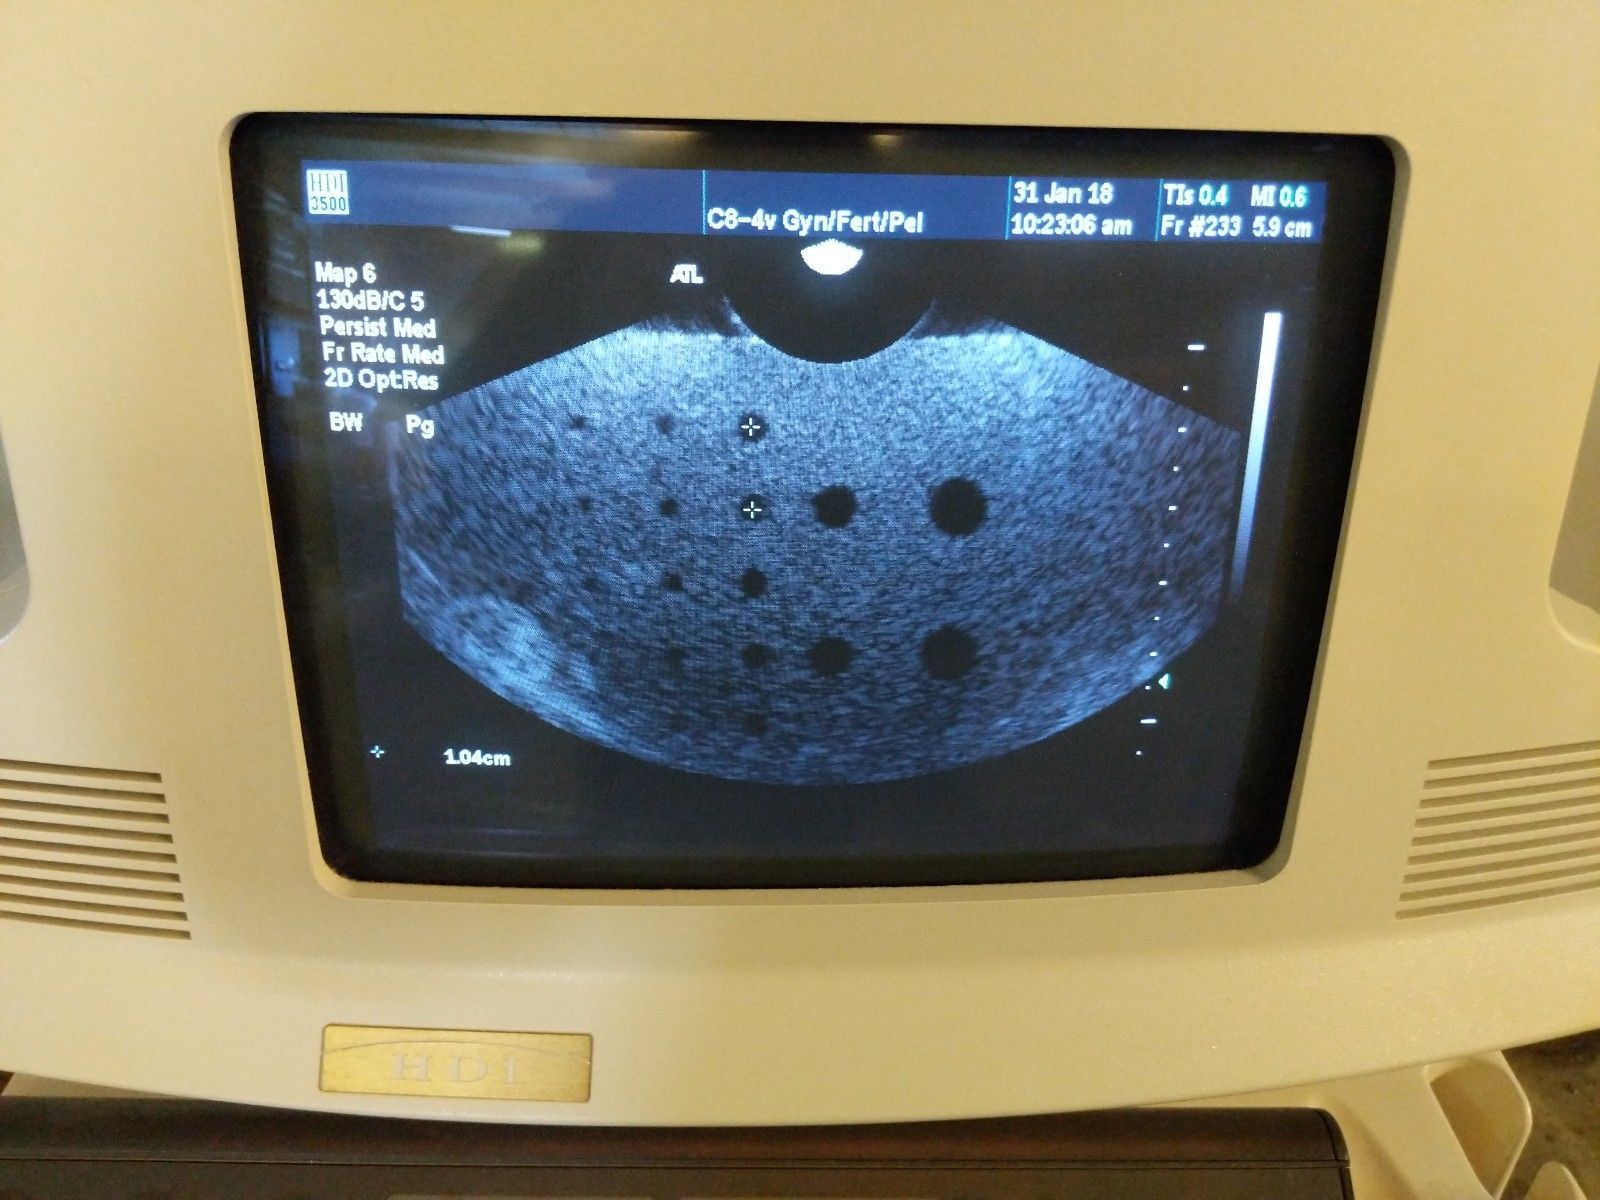

ATL HDI 3500 w/ 2 Probes

Condition:Used : An item that has been used previously. The item may have some signs of cosmetic wear, but is fully operational and functions as intended. This item may be a floor model or store return that has been used. See the sellerâs listing for full details and description of any imperfections. See all condition definitions- opens in a new window or tab

Seller Notes:âSystems have been powered on and tested. Additional tests may be performed. All systems will leave in described condition with no warranties expressed or implied.â

Brand: ATL

Model: HDI 3500